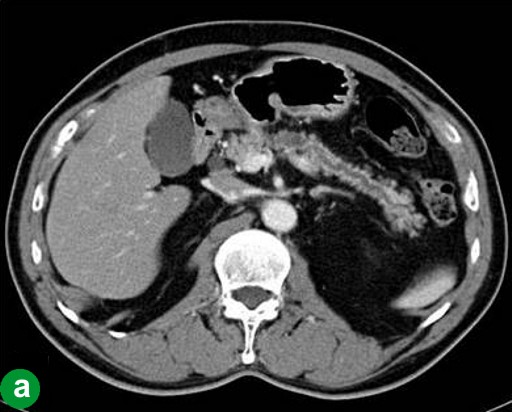

A 67-year-old man showed a pancreatic tumor on abdominal US at an annual medical checkup. An abdominal CT scan detected a 1 cm tumor in the body of the pancreas and main pancreatic duct dilatation of the distal pancreas (Figure 3a). A distal pancreatectomy with splenectomy was performed in February 2006. Histopathological examination confirmed a well-differentiated adenocarcinoma with no vessel or lymph duct invasion and no lymph node metastasis (Figure 3b). Mild atypical epithelia were observed at the cut edge of the main pancreatic duct (T1N0M0; R0; pathological stage: IA) (Figure 3c). Periodic checkups without adjuvant chemotherapy were carried out for 2 years, and there were no abnormal findings in abdominal CT scans or tumor marker assays.

|

Figure 3. Case#2: initial operation. a. A tumor approximately 1 cm in diameter and main pancreatic duct dilatation of the distal pancreas was detected in the pancreatic body on abdominal CT. b. Adenocarcinoma of the pancreas. Atypical cells with a swollen nucleus formed a papillary projection. c. Mild atypical epithelia projected from the cut edge of the main pancreatic duct. (H&E stain, x100). |